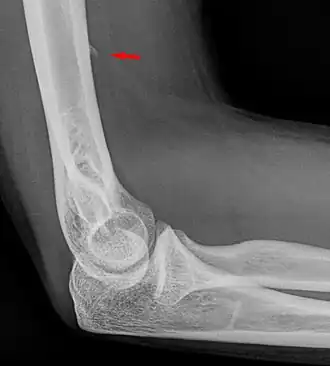

![]() Small supracondylar process seen on a lateral radiograph of the elbow | |

The supracondylar process of the humerus (also known as an avian spur) is a variant bony projection on the anteromedial aspect of the upper arm bone (humerus), about 5–6 cm above the medial epicondyle.[1] It is directed downward, forward and medially pointing to the medial epicondyle. A fibrous band, Struthers ligament, may connect this process to the medial epicondyle.[2] This variation has a prevalence of 0.68% and is significantly more common in women than in men.[3]